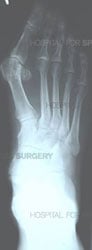

Orthopedic surgeons diagnose bunions on the basis of a physical examination and X-rays taken while the person is weightbearing (standing). Two angles are assessed:

- Intermetatarsal angle – the angle between the first and second metatarsals (the bones that lead up to the bases of the big toe and second toe). If this angle is wider than nine degrees (9º), it is abnormal and referred to as metatarsus primus varus.

- Hallux valgus angle – the angle of the big toe as it drifts toward the small toe. An angle that exceeds 15º is considered to be a sign of hallux valgus.